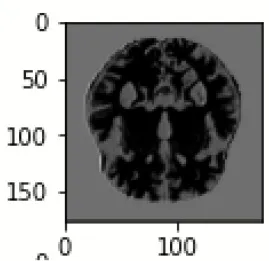

The database used in this study consists of a total of 6,200 AD images that are retrieved from the Kaggle database. It comprises grayscale images of 896 MD, 64 Mod D, 3,200 ND, and 1,966 VMD images, with a dimension of (208 × 176 × 3) pixels. The dataset for evaluation is divided in such a way that 80% of the image samples are utilized for training the model and the remaining 20% are utilized for testing the model (Filipovych et al., 2011). Figure 2 shows the database of MRI images. Table 2 shows the publicly available AD dataset.

FIGURE 2

www.frontiersin.org

Figure 2. Alzheimer's disease: (A) M.D, (B) Mod.D, (C) N.D, and (D) V.M.D.